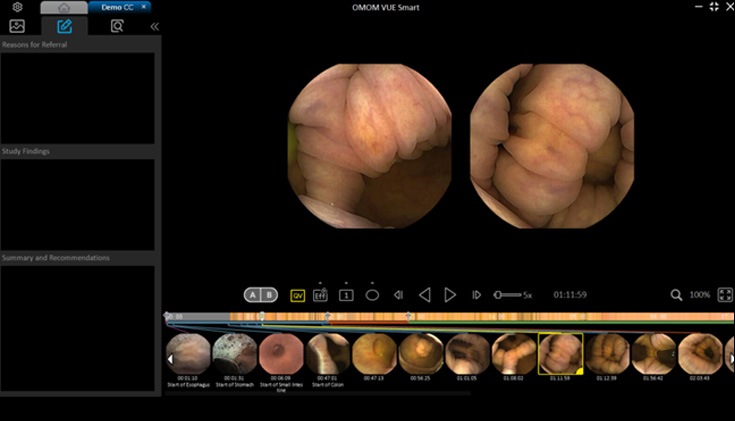

Vue Smart™

Wykorzystując zastrzeżone algorytmy sztucznej inteligencji, SmartScan przetwarza surowe pliki obrazów, usuwając do 90% nadmiarowości, identyfikując i oznaczając aż 16 rodzajów nieprawidłowości.

Tryb czytania SmartView odtwarza tylko obrazy pobrane przez Smartscan, pomagając nam szybciej poruszać się po całym filmie. Dzięki temu możemy przyspieszyć proces diagnostyczny.

Tryb czytania SmartView odtwarza tylko obrazy pobrane przez Smartscan, pomagając nam szybciej poruszać się po całym filmie. Dzięki temu możemy przyspieszyć proces diagnostyczny.